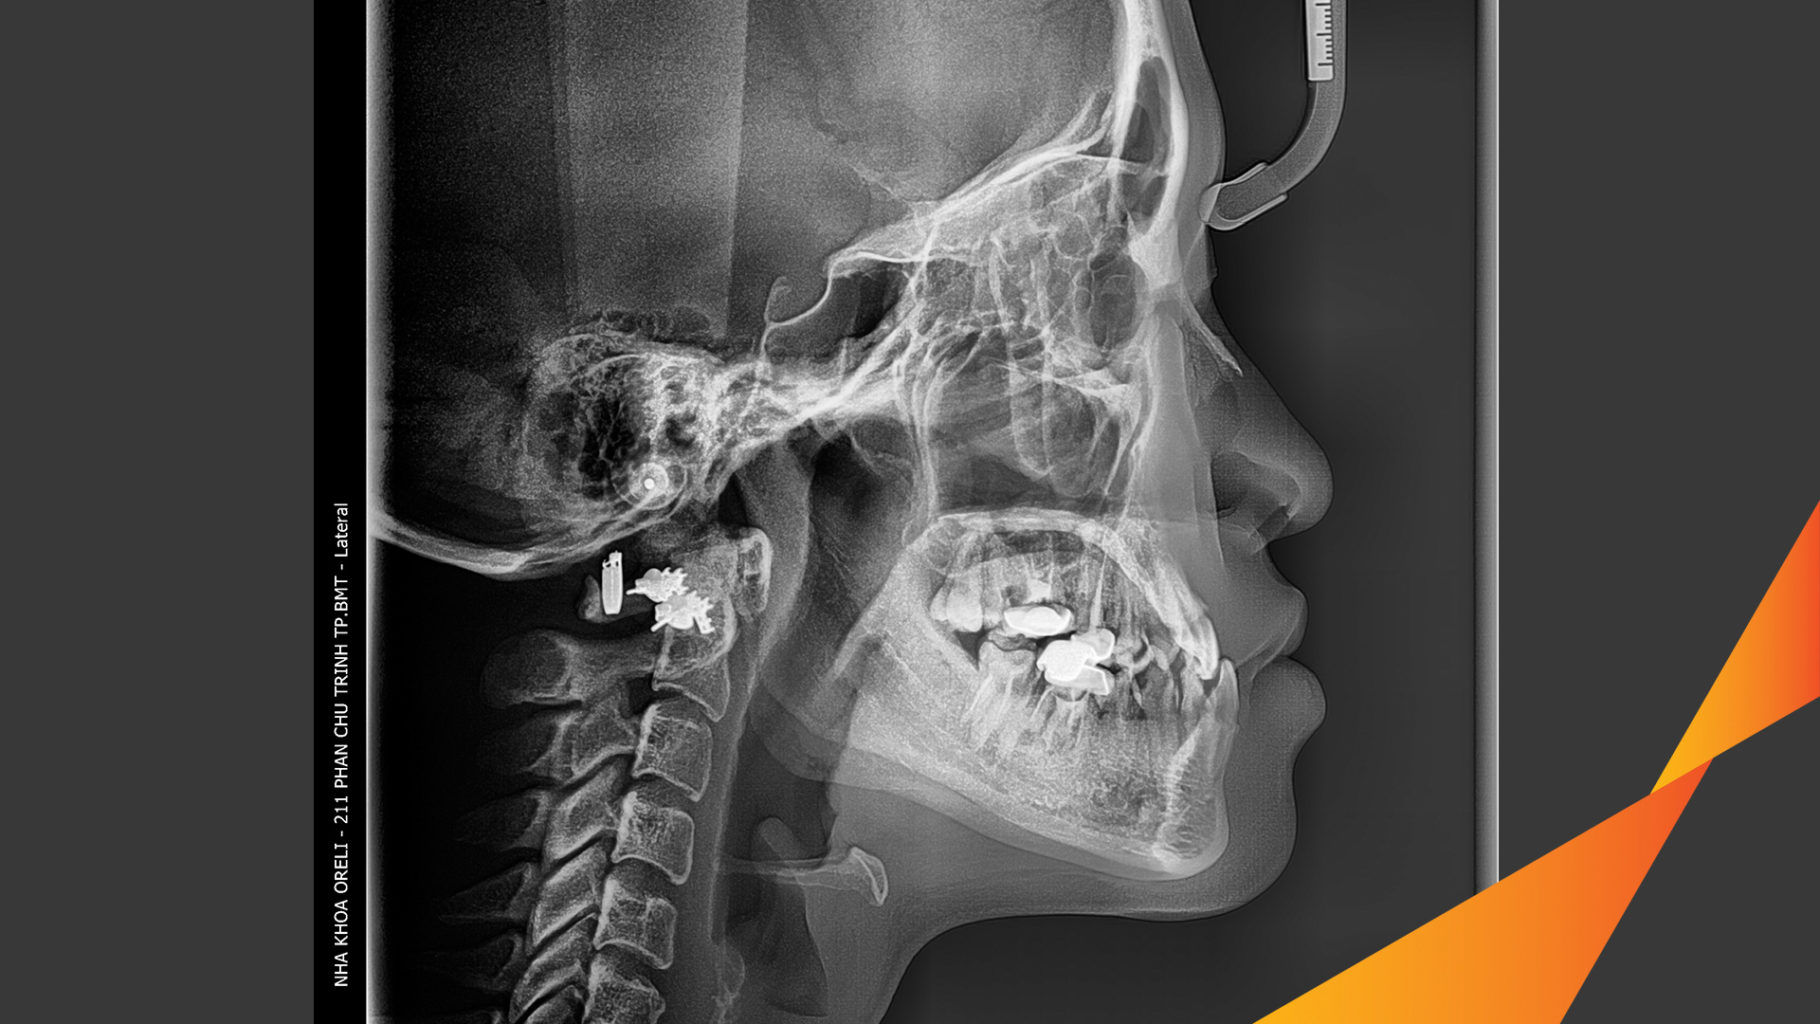

Ca niềng hạng 3 móm di gần răng 78 cho nụ cười đẹp ở Oreli

Ca niềng răng di gần răng 7 8 phục hồi ăn nhai và thẩm mỹ nụ cười. Kết quả thực tế trước và sau điều trị tại Nha khoa Oreli.